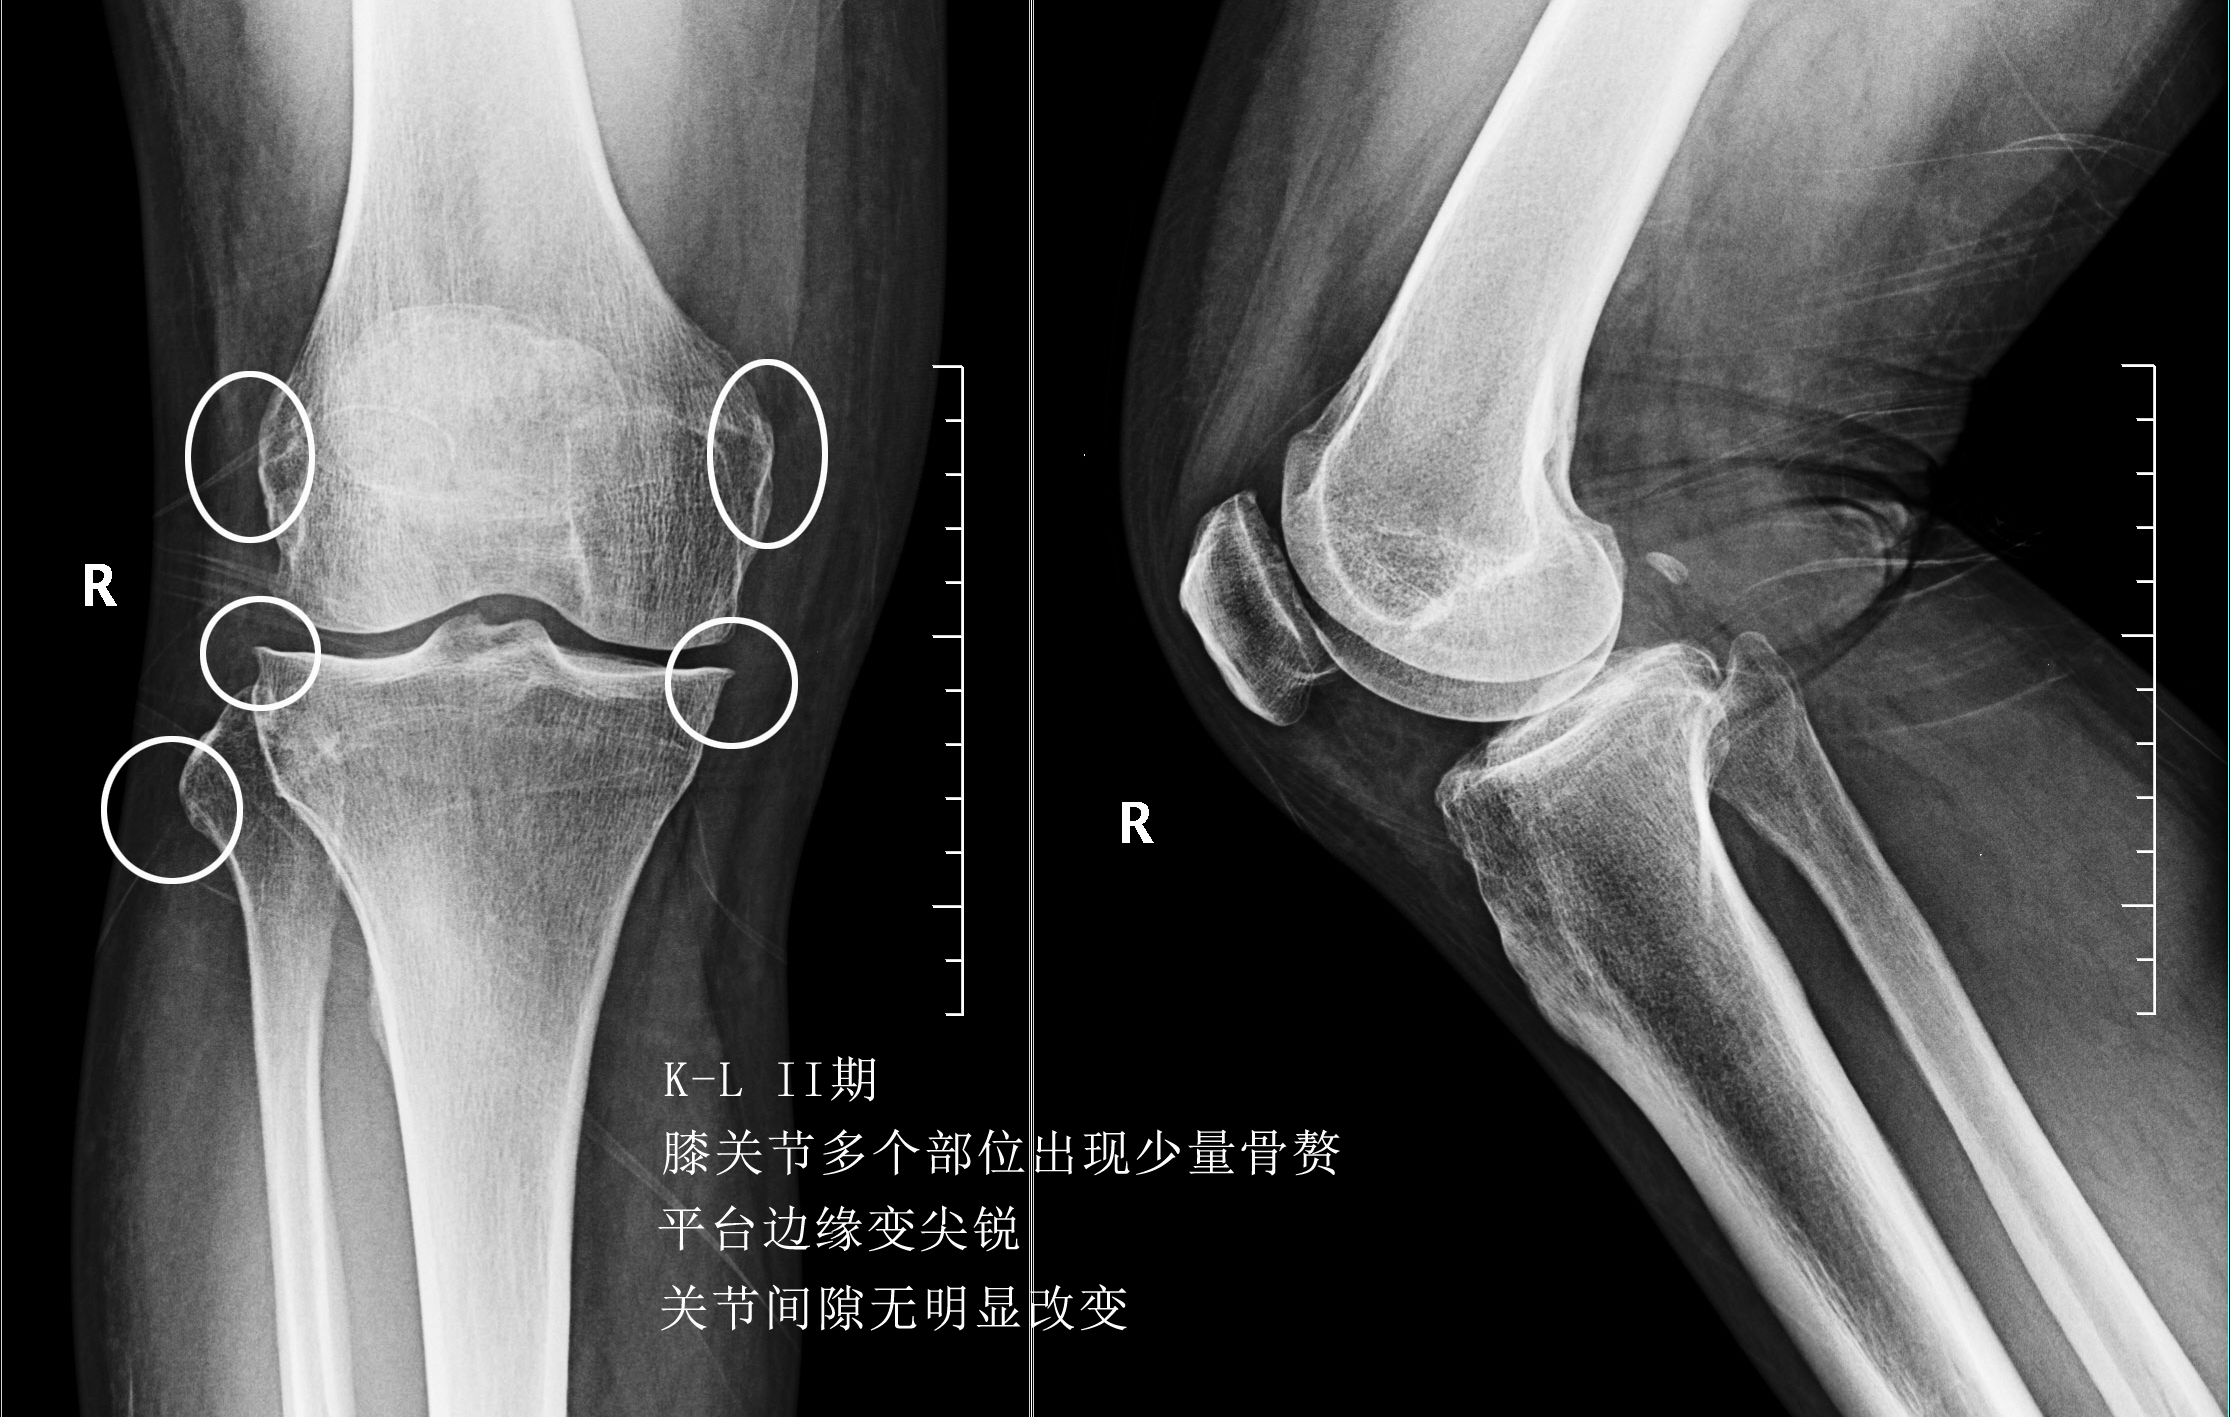

前面已经说到骨关节炎会导致骨赘的形成以及关节间隙的狭窄,所以我们依靠膝关节x片子来初步判断骨关节炎的病情,通常我们采用K_L分期判断病情。

二期患者:2期的患者关节的那个骨赘就已经开始明显增多了,但是这个时期关节的间隙仍然不会发生狭窄,这就说明关节内的软骨虽然已经有了磨损,但是磨损的程度还可以,不是特别的重。

往往这个时期的患者,如果症状比较明显,在医院检查发现了骨关节炎,治疗起来反而效果最好。因为关节的软骨还没有磨损的特别严重,此时我们通常可以采取给于关节内进行玻璃酸钠、几丁糖或者是富血小板血浆因子注射的办法来减缓软骨磨损的进程,缓解患者的症状。此时也可以给予患者口服氨糖。